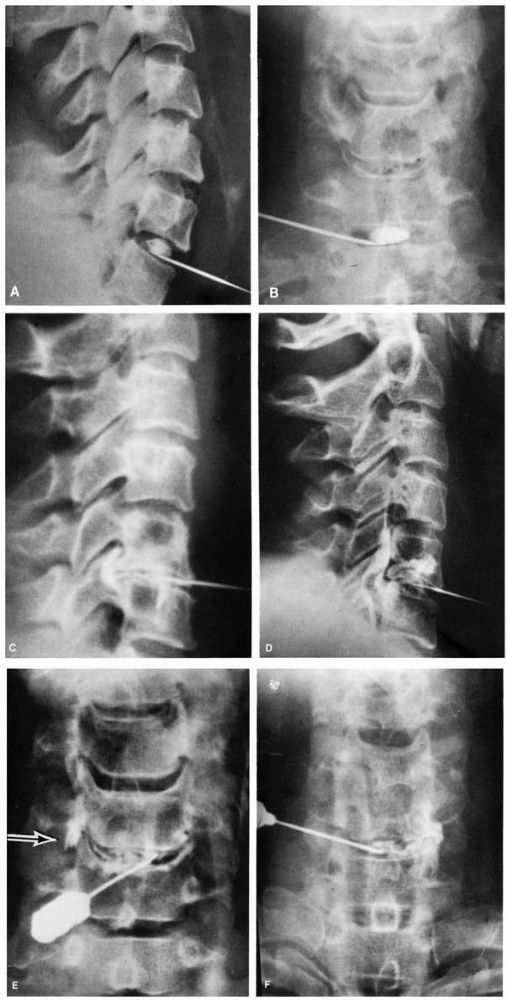

![]() |

FIGURE 11-4.

Degenerative arthritic changes in the cervical spine following loss of disc material particularly between C5 and C6. However, the oblique view shows spur formation encroaching on the intervertebral foramina from C3 to C7, which can cause nerve root symptoms. |

and extension views (Figure 11-4). Look for

evidence of foraminal encroachment, vertebral malalignment, sclerosis,

facet joint subluxation, osteophyte protrusions, destructive changes

within the disc or vertebral body, and ossification of the posterior

longitudinal ligament. Canal dimensions can be inferred by measuring

the Torg ratio of canal width (posterior vertebral body to posterior

laminar line) to vertebral body, with anything less than 0.8 is

considered stenosis. Further evaluation may include MRI, myelography

using water-soluble contrast followed by contrast-enhanced CT scanning.